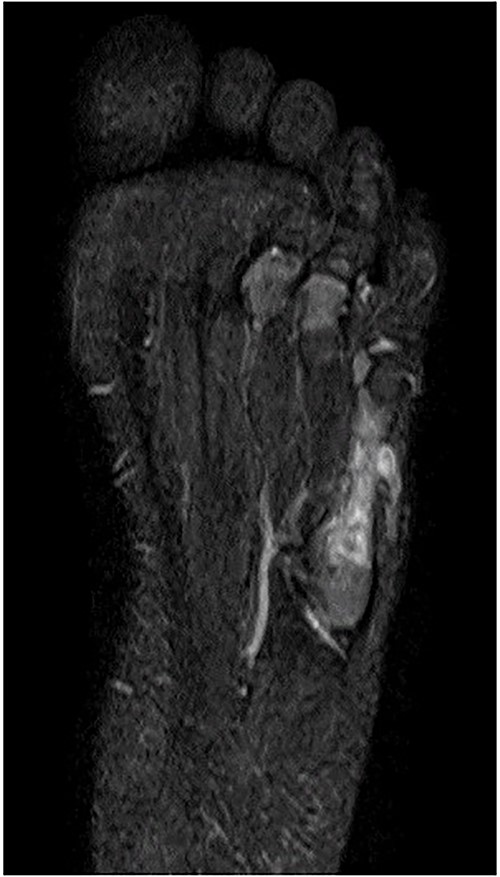

A 21-month-old Japanese female infant presented with a swollen mass on the dorsolateral aspect of the left foot. Her parents noticed the mass and brought the patient to our hospital. The patient had no past medical histories or complications prior to the occurrence. In addition, she received the BCG vaccine at the age of 4 months in Japan. At first visit to our hospital, physical examination revealed the ~3 × 3 cm mass was located on the dorsolateral aspect of the left foot and was hard accompanied by local heat (Fig. 1). Plain radiographs of the left foot showed a lytic lesion without periosteal reaction in the fifth metatarsal bone (Fig. 2). Magnetic resonance imaging (MRI) showed an isointense lesion on T1-weighted images and a hyperintense lesion on T2-weighted images around and within fifth metatarsal (Fig. 3). Gallium scintigraphy revealed intense uptake in the patient’s left foot (Fig. 4). In addition, laboratory examination was within normal. Based on medical history, clinical and imaging findings, we considered the possibility of neoplasia or osteomyelitis and performed an open debridement and biopsy of the lesion to make a diagnosis. The lesion was yellow and consisted of weak, adipose-like tissue that surrounded and continued into the inferior of the fifth metatarsal bone (Fig. 5). The lesion inside and outside the bone was resected as much as possible. Histopathologic examination of the lesion showed granulomatous inflammation including anaplastic giant cells, Langerhans-type giant cells and caseous necrosis (Fig. 6). Based on these results, TB or BCG osteomyelitis was considered as a diagnosis. The tuberculin test was positive, but the QuantiFERON TB test was negative. In addition, samples analyzed using polymerase chain reaction did not identify M. tuberculosis, but did identify the BCG Tokyo-172 strain. Per these findings, the patient was diagnosed with BCG osteomyelitis of the fifth metatarsal and oral treatment with anti-TB medicine including isoniazid (100 mg/day) and rifampicin (150 mg/day) was started. Clinical findings included reduction in swelling of the mass and gradual remodeling of the lytic lesion of the fifth metatarsal on plain radiographs (Fig. 7). However, 10 months after starting the anti-TB treatment, the mass recurred, and MRI revealed a residual high-intensity lesion around and inside the fifth metatarsal on T2-weighted fat-suppressed images (Fig. 8). It was determined that the lesion was difficult to control with anti-TB treatment alone, so an open debridement for the lesion was performed again. Histopathologic examination of the lesion revealed an epithelioid granuloma with necrosis. Therefore, the anti-TB treatment was continued. Six months after the second surgery, clinical and radiographic image findings showed complete improvement (Fig. 9). As a result, anti-TB treatment was ended. At the time of writing this report, 8 years after starting anti-TB treatment, there has been no recurrence.

MRI showed an isointense lesion on T1-weighted images and a hyperintense lesion on T2-weighted images around and within the fifth metatarsal.